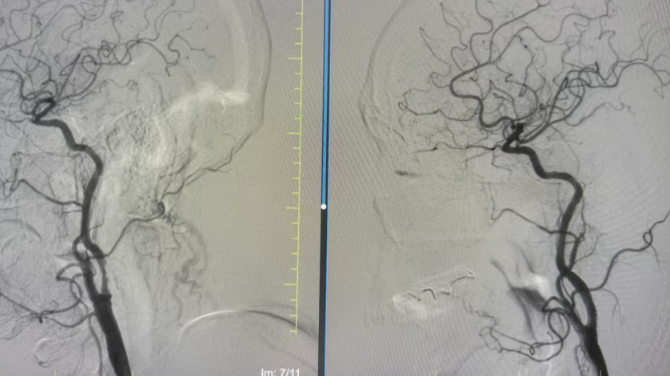

盡管方大爺年事已高,但手術(shù)的獲益遠大于風險。在醫(yī)護團隊詳細告知病情、手術(shù)流程及風險后,方大爺及家屬果斷決定接受血管內(nèi)介入治療。完善術(shù)前準備后,手術(shù)在局部麻醉下順利開展,介入團隊憑借精湛的技術(shù),精準定位血管狹窄部位,平穩(wěn)將支架送入并成功釋放,狹窄血管被順利撐開,充沛的血流重新順暢灌注大腦,為方大爺?shù)纳袠小袄m(xù)航”。